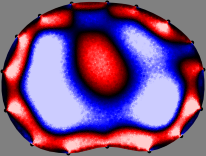

To explain the FER method, we closely examine the correlations among column vectors of the sensitivity matrix , described in Fig. 2. The correlation between and can be expressed as

for [23]. This shows that the column vector is like an EEG (electroencephalography) data induced by dipole sources with directions at locations . Given that two dipole sources at distant locations produce mutually independent data, the correlation between and decreases with the distance between and . Fig. 2 shows a few images of the correlation as a function of for four different positions . The correlation decreases rapidly as the distance increases. In the green regions where the correlation is almost zero, is nearly orthogonal to .

Fig. 2 shows that if and are far from each other, the corresponding columns of the sensitivity matrix are nearly orthogonal. This somewhat orthogonal structure of the sensitivity matrix motivates an algebraic formula that directly computes the local ensemble average of conductivity changes at each point using the inner product between changes in the data and a scaled sensitivity vector at that point: